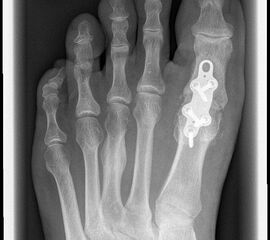

Das nachfolgend präsentierte OP-Verfahren zeigt die Großzehengrundgelenkarthrodese mit Gelenkflächenpräparation mittels sogennanter „Cup-and-Cone“-Fräsen und einer dorsal angebrachten variablen winkelstabilen Platte mit Gleit-/Kompressionsloch.

Durch die Verwendung sogenannter „Cup-and-Cone“-Fräsen und die Osteosynthese mit winkelstabiler Platte ggf. in Kombination mit einer interfragmentären Zugschraube kann die Rate der Pseudarthrosen vor allem bei schlechten Knochenverhältnissen deutlich reduziert werden, sodass dieses Verfahren zunehmend empfohlen wird 9.

• Röntgen-Kontrolle der Osteosynthese und Stellung intraoperativ / postoperativ, nach 3 Wochen und nach 6 Wochen

Pseudarthrose: Verzögerte Knochenheilung und Pseudarthrosen treten je nach Osteosynthesetechnik unterschiedlich häufig auf. Bei Verwendung von Drähten oder Drahtcerclagen werden hohe Pseudarthroseraten von über 13% beschrieben, daher sollten diese Verfahren verlassen werden1021. Einzelschrauben bieten keine ausreichende Rotationsstabilität und werden daher nur noch selten verwendet. Korrekt eingebrachte gekreuzte Schrauben ergeben zwar bei primärem Hallux rigidus und guter Knochenqulität eine hohe Stabilität, sind jedoch bei osteopenischem Knochen und vor allem bei rheumatoider Arthritis oft unzureichend 141516. Die Rate an Pseudarthrosen kann hier durch Plattenosteosynthese mit interfragmentärer Zugschraube oder mit winkelstabiler Platte mit Gleit-/Kompressionsloch deutlich gesenkt werden 622. Nachteilig ist die Materialstärke der winkelstabilen Platte die zum Teil vermehrt aufträgt und daher gelegentlich die Metallentfernung notwendig macht.